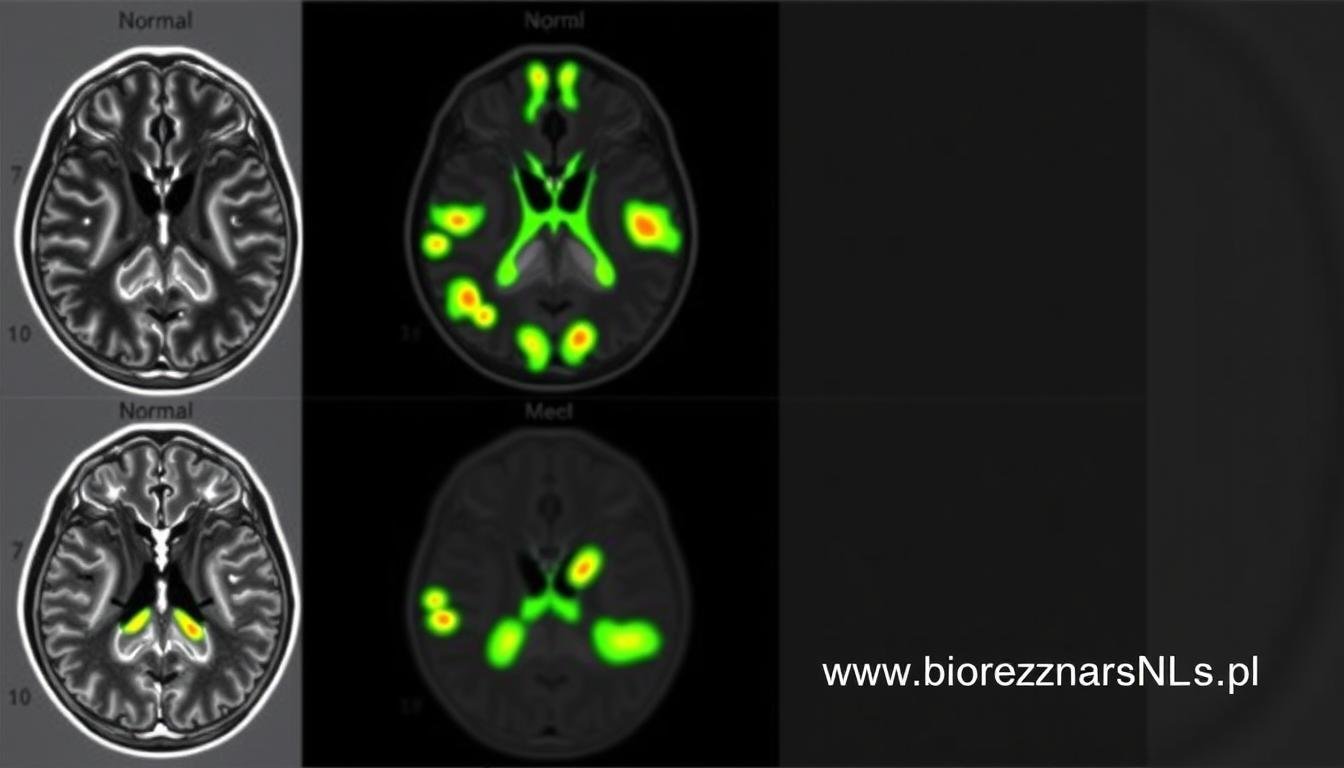

| Stwardnienie rozsiane | Wykrywanie ognisk demielinizacji, ocena stanu układu immunologicznego | Nieinwazyjność, możliwość częstego monitorowania zmian |

Stwardnienie rozsiane (SM) to przewlekła choroba autoimmunologiczna, w której układ odpornościowy atakuje osłonki mielinowe neuronów. Wczesna diagnostyka ma kluczowe znaczenie dla skutecznego leczenia. Biorezonans NLS umożliwia wykrycie subtelnych zmian w strukturze mieliny, zanim staną się one widoczne w badaniach MRI.

Pacjent, 58 lat, zgłosił się z niespecyficznymi objawami: okresowym drżeniem rąk i niewielkimi zaburzeniami równowagi. Konwencjonalne badania neurologiczne nie wykazały jednoznacznych nieprawidłowości. Badanie Biorezonansem NLS ujawniło subtelne zmiany w funkcjonowaniu jąder podstawy mózgu, charakterystyczne dla wczesnego stadium choroby Parkinsona.

Diagnostyka neurologiczna dysponuje szeregiem metod badawczych, od badania klinicznego po zaawansowane techniki obrazowania. Biorezonans NLS nie zastępuje tych metod, ale stanowi cenne ich uzupełnienie, oferując unikalne możliwości diagnostyczne.

| MRI (rezonans magnetyczny) | Obrazowanie struktury tkanek za pomocą pola magnetycznego | Wysoka rozdzielczość obrazu, dobra wizualizacja tkanek miękkich | Wysoki koszt, długi czas badania, przeciwwskazania (implanty metalowe) | Biorezonans NLS może wykryć zmiany funkcjonalne przed pojawieniem się zmian strukturalnych widocznych w MRI |

| EEG (elektroencefalografia) | Rejestracja aktywności elektrycznej mózgu | Nieinwazyjność, możliwość długotrwałego monitorowania | Ograniczona rozdzielczość przestrzenna, trudności interpretacyjne | Biorezonans NLS dostarcza informacji o metabolizmie i funkcjonowaniu komórek nerwowych |

| PET (pozytonowa tomografia emisyjna) | Obrazowanie metabolizmu tkanek | Ocena funkcjonalna, wykrywanie zmian metabolicznych | Wysoki koszt, ograniczona dostępność, ekspozycja na promieniowanie | Biorezonans NLS oferuje podobne informacje funkcjonalne bez narażenia na promieniowanie |